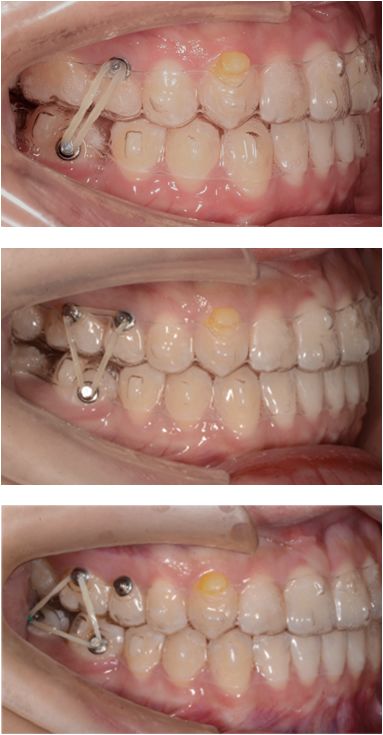

第5副,II类牵引来辅助47牙前移,给它部分垂直向分力,但由于水平向上分力更大,使其更前倾,我们停止了长牵引的佩戴。

第30副,改为局部牵引,根据牙齿移动的情况设计牵引,给予其更多的垂直向分力。

第34副矫治器时,48牙近远中和垂直向移动的情况不是太好,我们使用了一个三角形牵引,以矫治器作为引导,帮助它向近中合方移动。

反馈后37副矫治器后,我们完成了矫治,总疗程共30个月。在成功的磨牙长距离前移中,未辅助固定矫治。